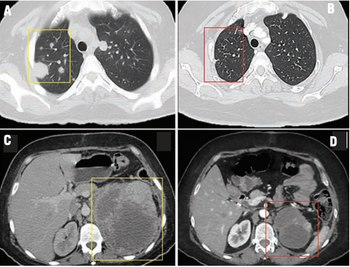

In this installement of Clinical Quandaries, Abigail Mateos-Soria, MD, and colleagues present a case of an 38-year-old woman who has a 3-month history of fatigue, dyspnea, significant weight loss, and severe left flank pain.